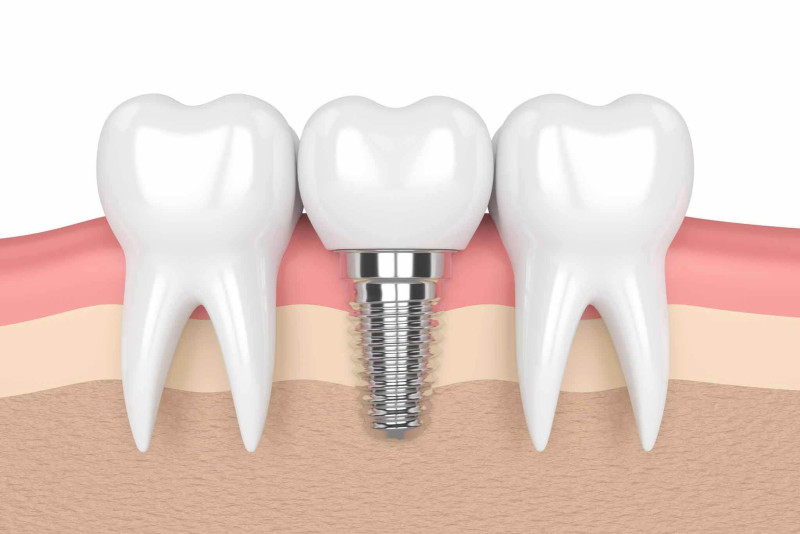

Ein Zahnimplantat ersetzt einen natürlichen Zahn mit Wurzel und soll über Jahre hinweg zum haltbaren Ersatz werden. Je nach individuellem Zustand der Zähne und des Gebisses gibt es vielfältige Möglichkeiten, Lücken zu schliessen. Beispielsweise kann der Zahnarzt mit einer Brücke, Krone oder anderen Lösungen Ihre Zahnreihe schliessen und Ihre Zahngesundheit erhalten oder wiederherstellen.